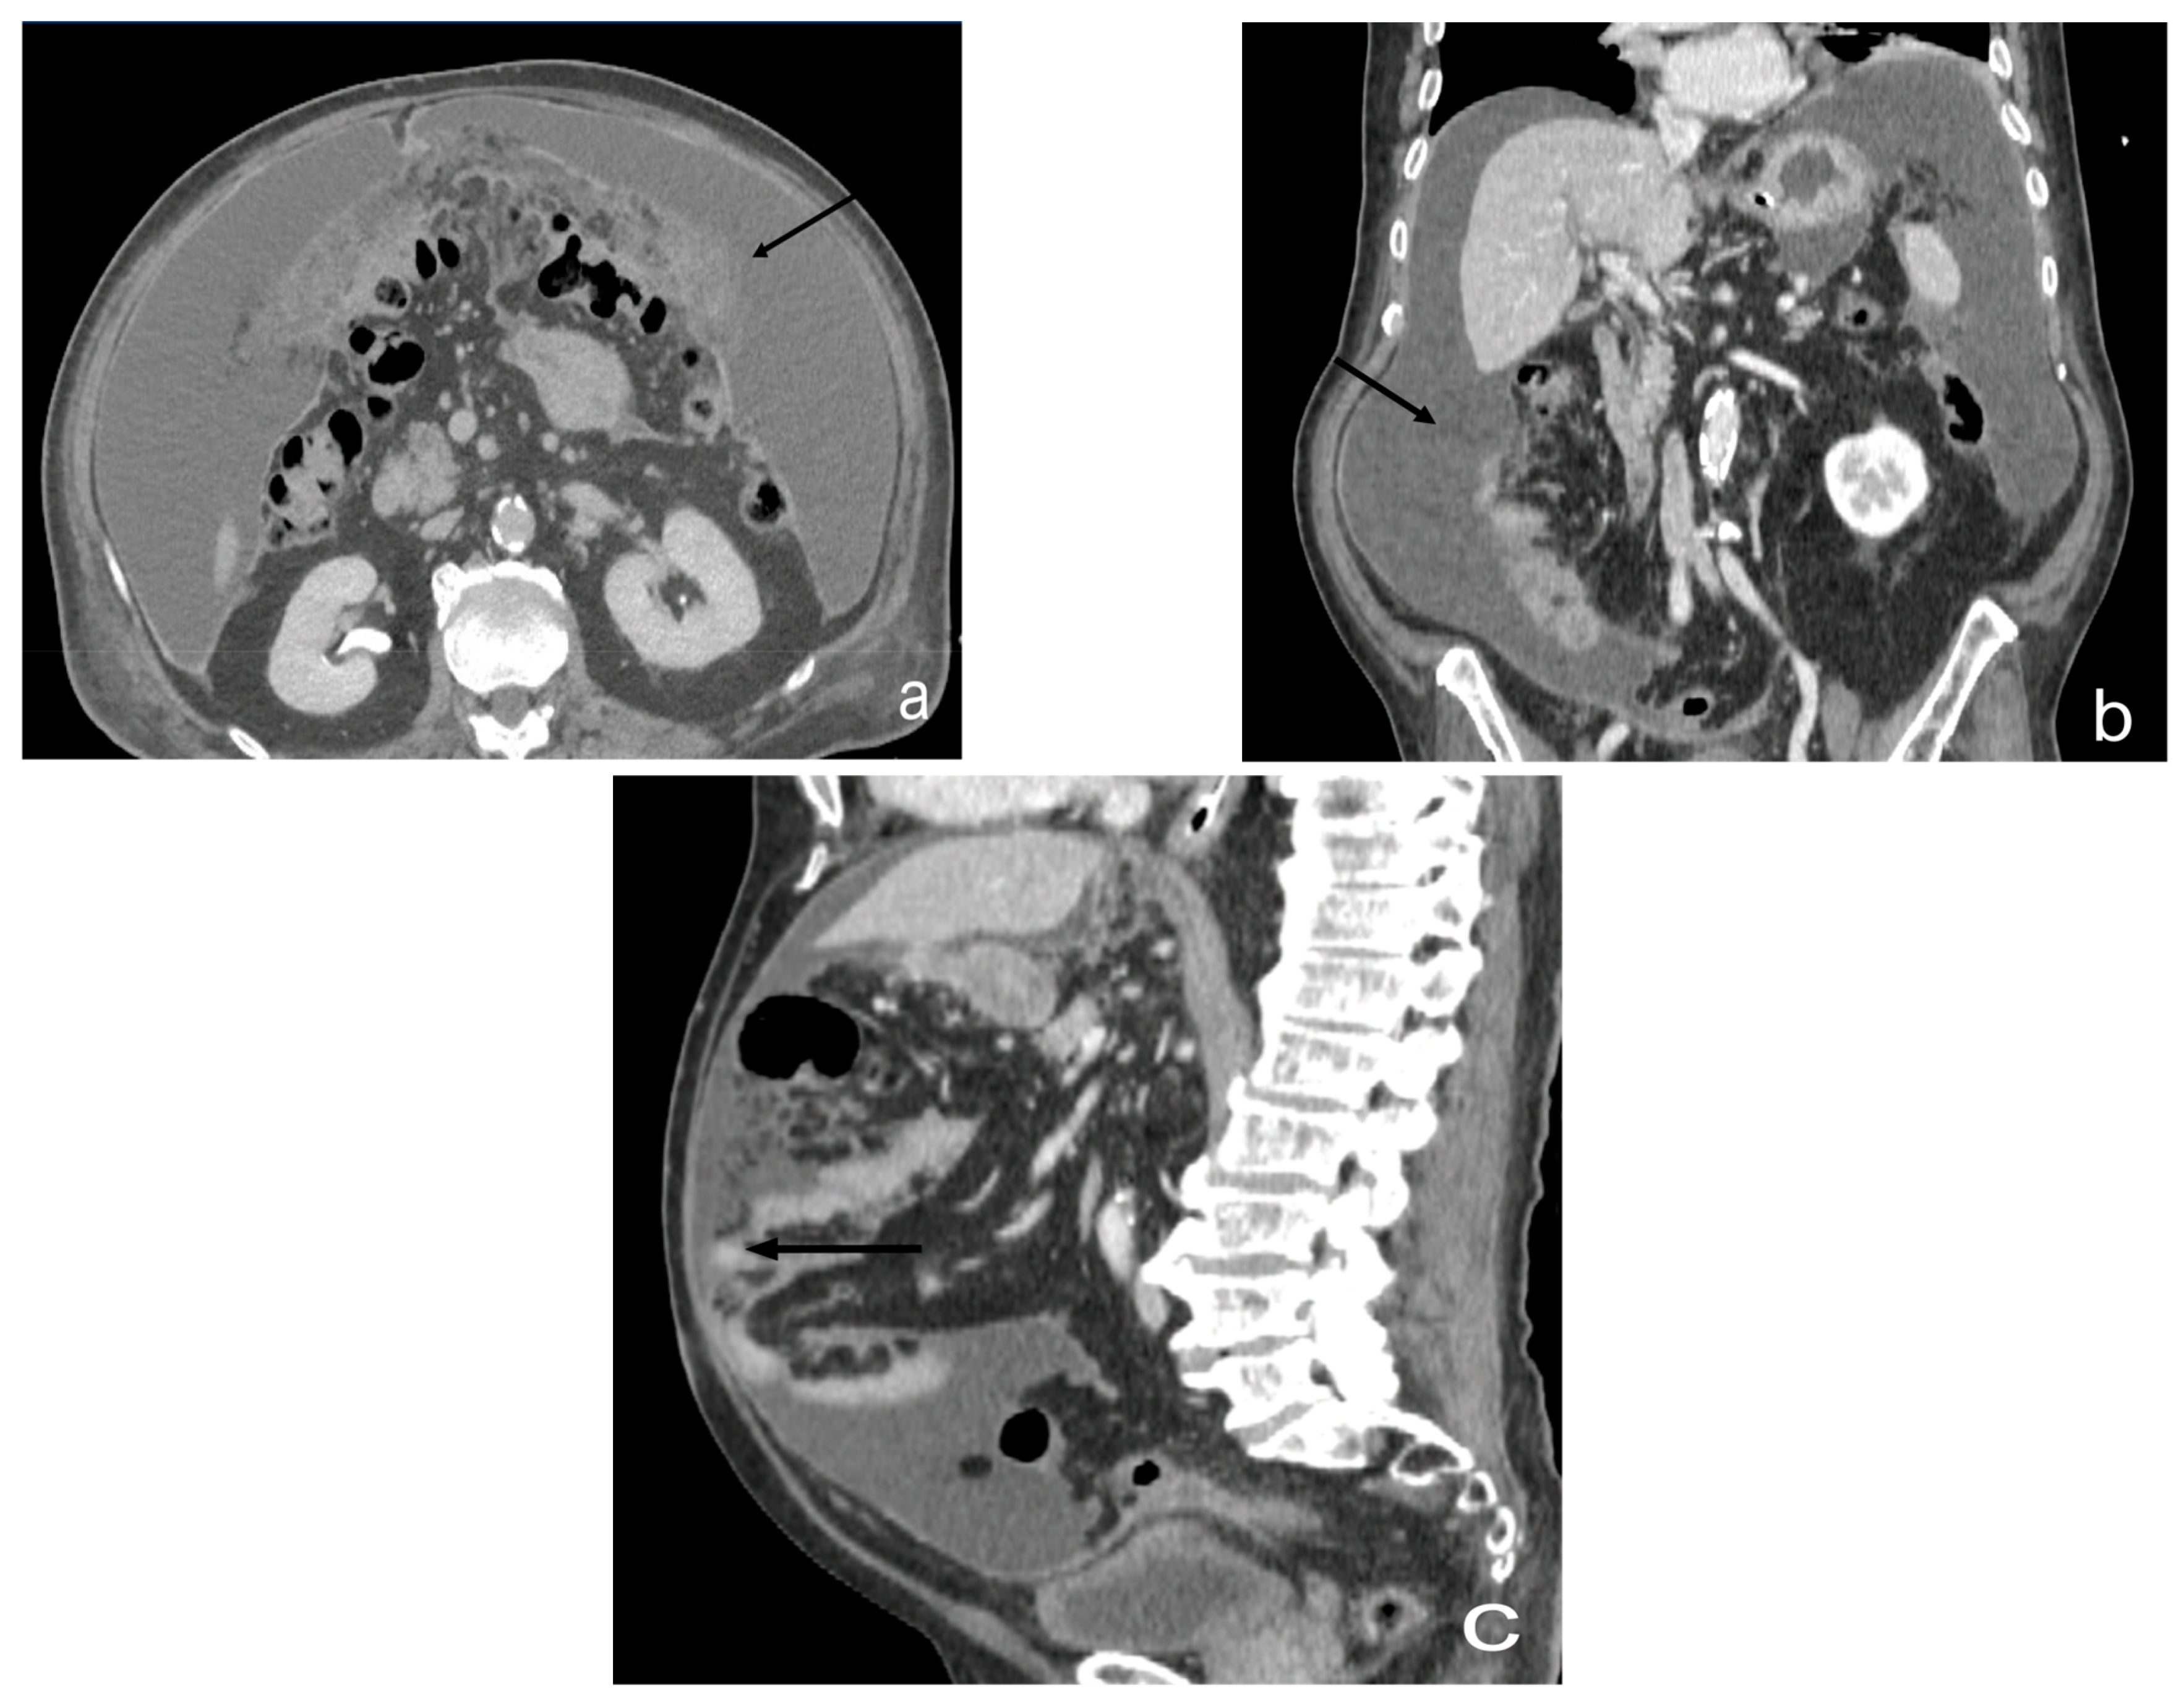

- Plaque pattern: confluent nodular tumor implants that are typically located on the lower surface of the right diaphragm and may manifest as a depression of the liver surface, mimicking capsular or subcapsular liver metastases. They present as areas of low attenuation relative to the parenchyma on postcontrast scans [94,95] (Figure 10).